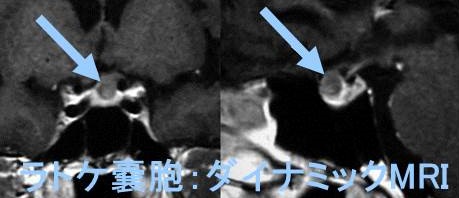

MRI検査では

- T1強調;50% 高信号(蛋白成分が多い)、50% 低信号

- T2強調;70% 高信号、30% 等-低信号

- T1+ Gd造影剤;造影効果なし、周囲辺縁のみ造影される